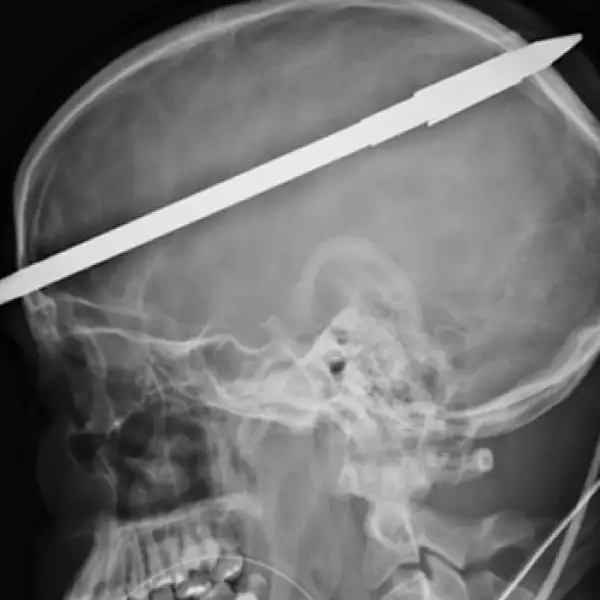

Un joven sobrevive luego de que un arpón de pesca atravesara su cráneo

Yasser López, logró sobrevivir después de que su amigo le disparara accidentalmente un arpón en un lago de Florida